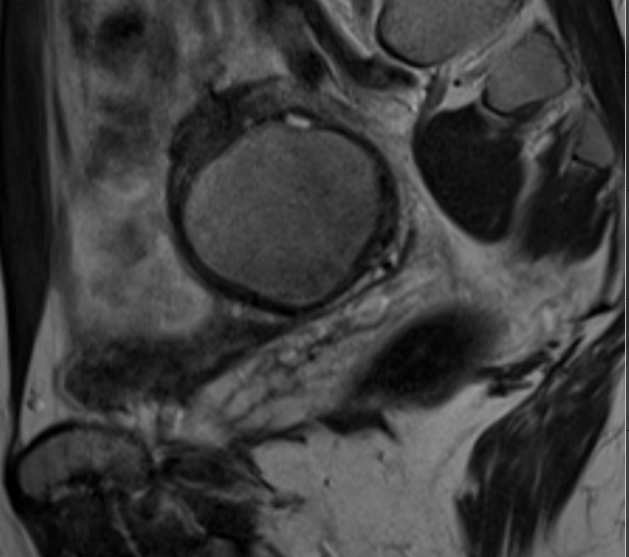

. Ressonància magnètica (RM).

És un examen que utilitza un camp magnètic i ones de ràdio per crear imatges detallades dels òrgans i teixits dins del cos. Una ressonància magnètica permet la planificació quirúrgica. Proporciona informació detallada al cirurgià sobre el lloc i la mida dels implants.

- endometriosis en Resonància

- endometrioma a la ressonància

- ressonància magnètica